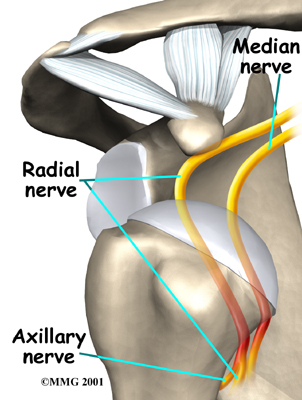

The shoulder may become so loose that it starts to dislocate frequently. This can be a real problem, especially if you can't get it back in the socket and must go to the emergency room every time. A shoulder dislocation is usually very obvious. The injury is very painful, and the shoulder looks abnormal. Any attempted shoulder movements cause extreme pain. A dislocated shoulder can damage the nerves around the shoulder joint.

If the nerves have been stretched, a numb spot may develop on the outside of the arm, just below the top point of the shoulder. Several of the shoulder muscles may become slightly weak until the nerve recovers. But the weakness is usually temporary.